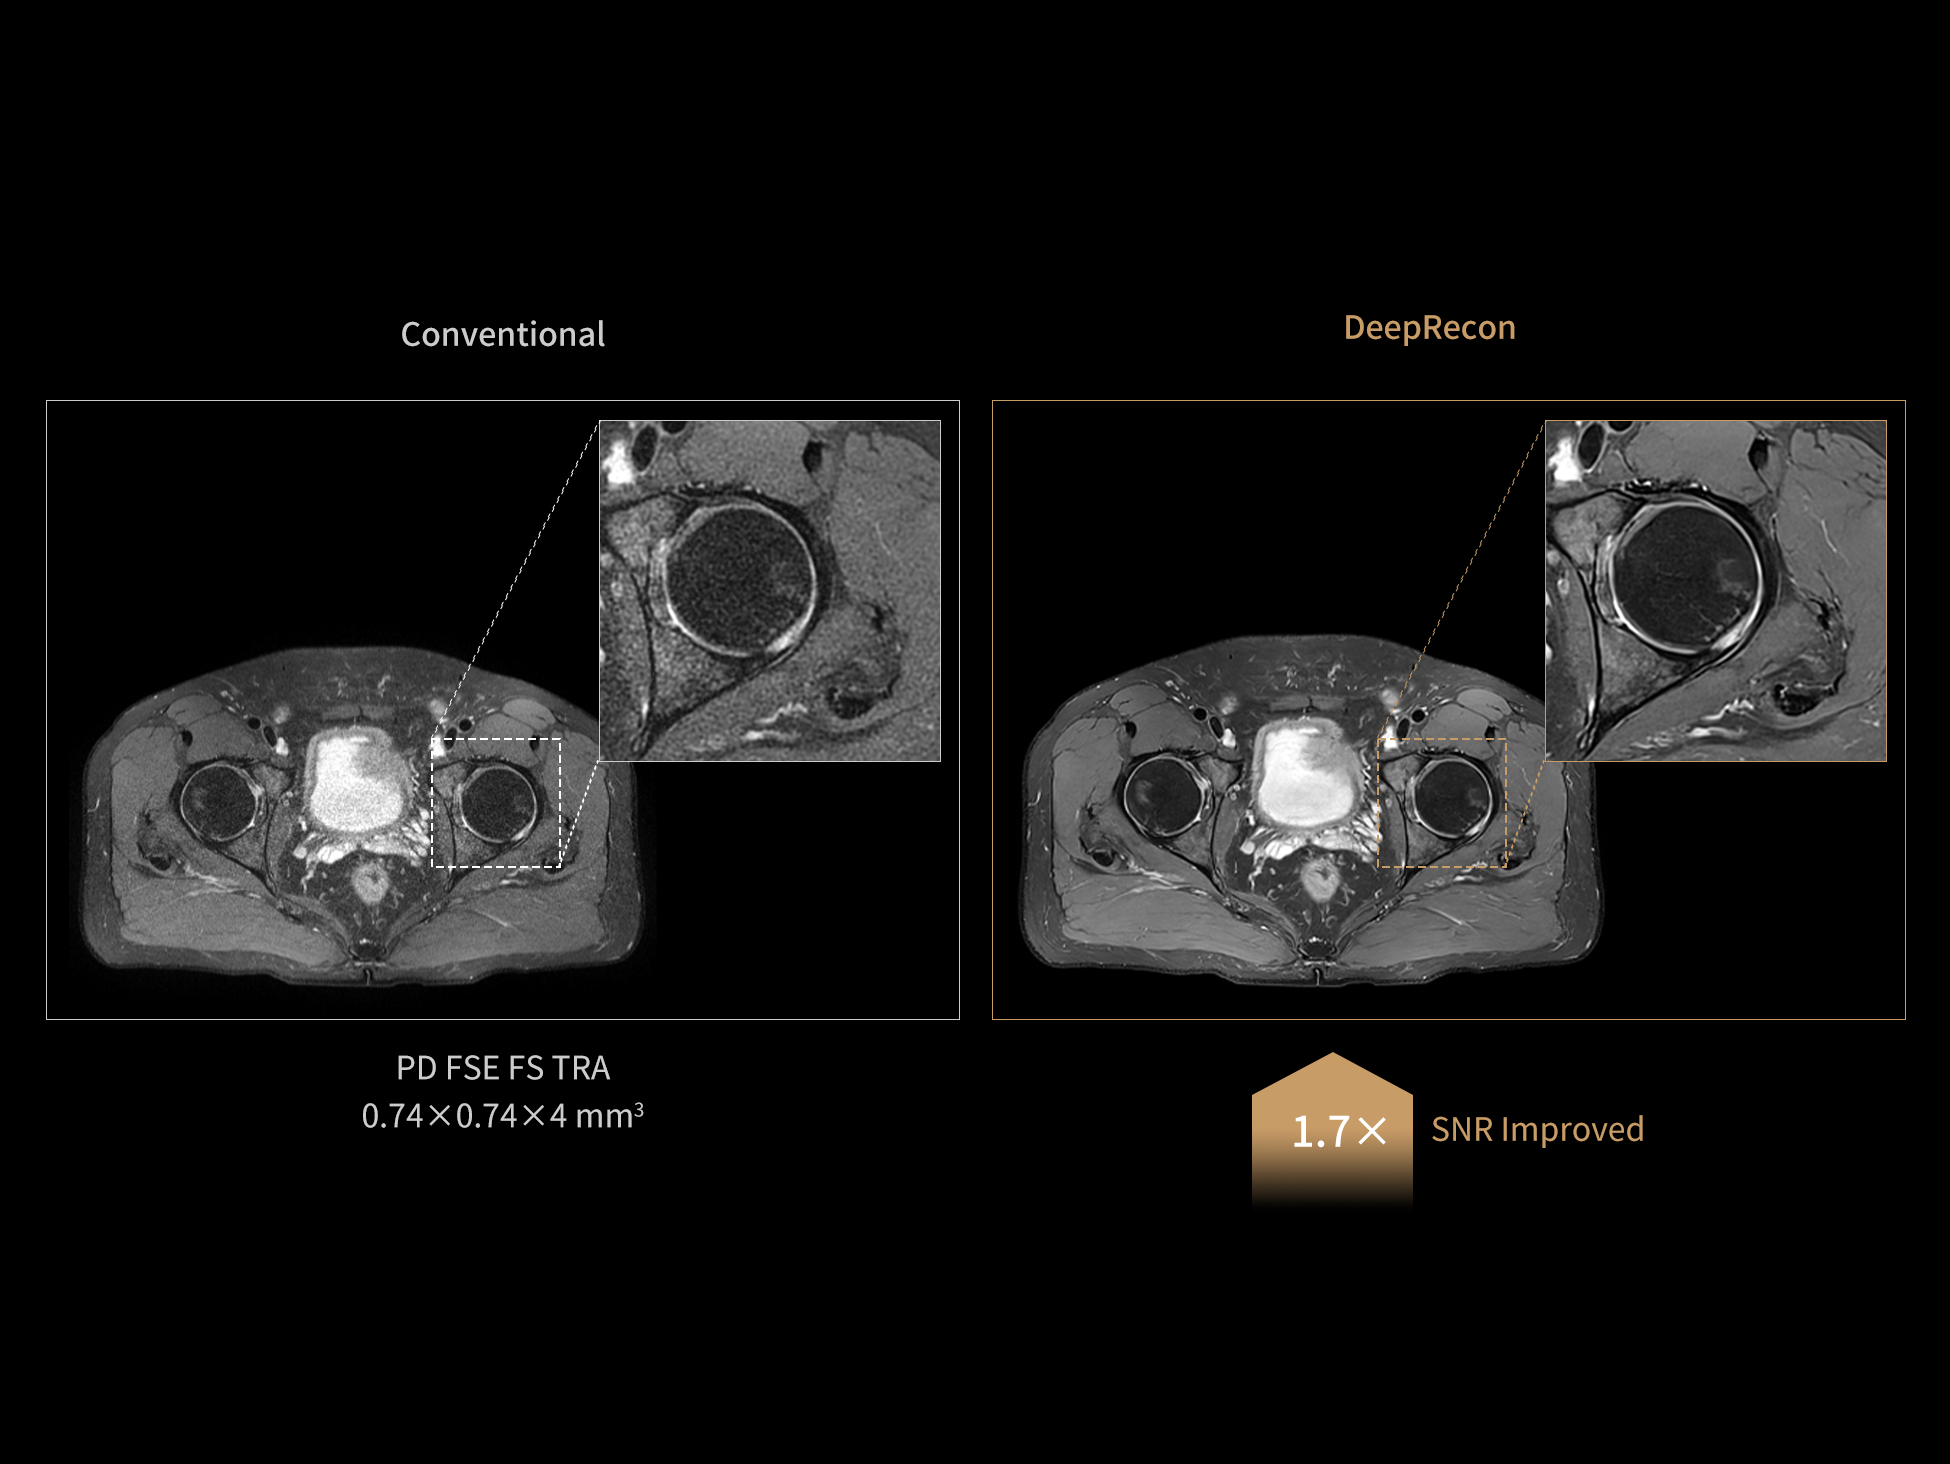

Using the same protocol, DeepRecon is capable of significantly enhancing the signal-to-noise ratio (SNR) and providing rich image details.

Images courtesy of United Imaging.